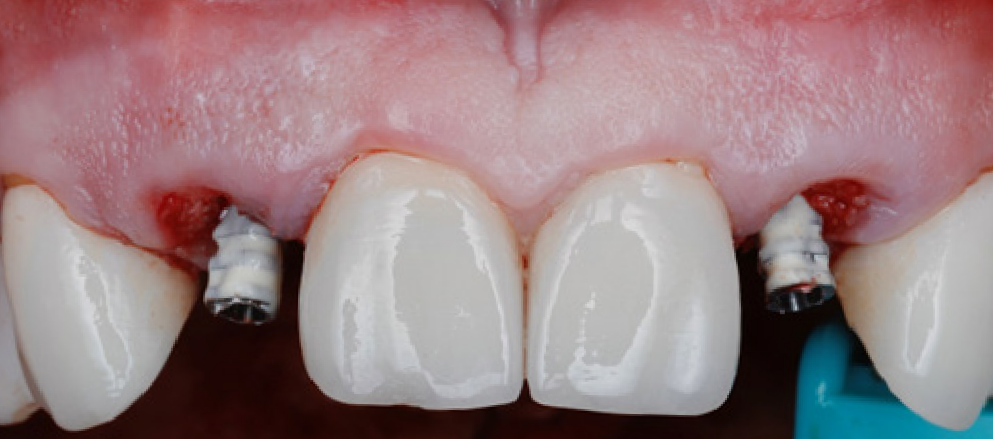

Once the temporary is picked up and emergence profile is customized to have an adequate regenerative space and properly placed Critical contour (0.5 short of the final gingival margin) we are ready to deliver the prosthesis.

Prior to delivery make sure to leave a good amount of room in the embrasures to allow for soft tissue fill during the training period.

Upon delivery of the prosthesis, some blanching is a good sine of tissue compression in needed areas (usually proximally) which starts the process of tissue training.

After 3 months of tissue training, patient returned for his final evaluation prior to final restoration.